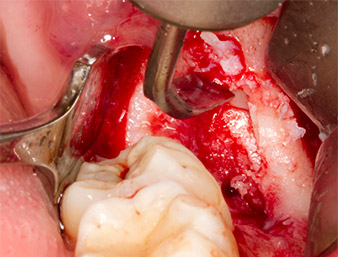

Per ottenere materiale autogeno per il successivo trattamento della ferita, sono stati estratti frammenti di osso sano nella zona del residuo di radice con uno strumento piezochirurgico (Piezomed B5) (Fig. 5).

Il tessuto autogeno è stato rimosso con la sezione a forma di raschietto della parte funzionante dello strumento e conservato un una soluzione salina fisiologica per uso successivo (vedere Fig. 13).